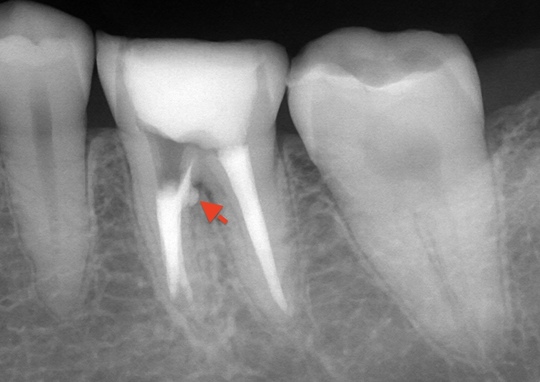

自費根管治療症例2 治療前

左下の奥歯が根の治療を受けているが治らない。

管の分かれている部分に根の治療による穿孔がありました

穿孔部分の封鎖と通常の根管治療を行いました

症状は、完全に消えて、穿孔部分の封鎖と確実な清掃、充填が確認できます